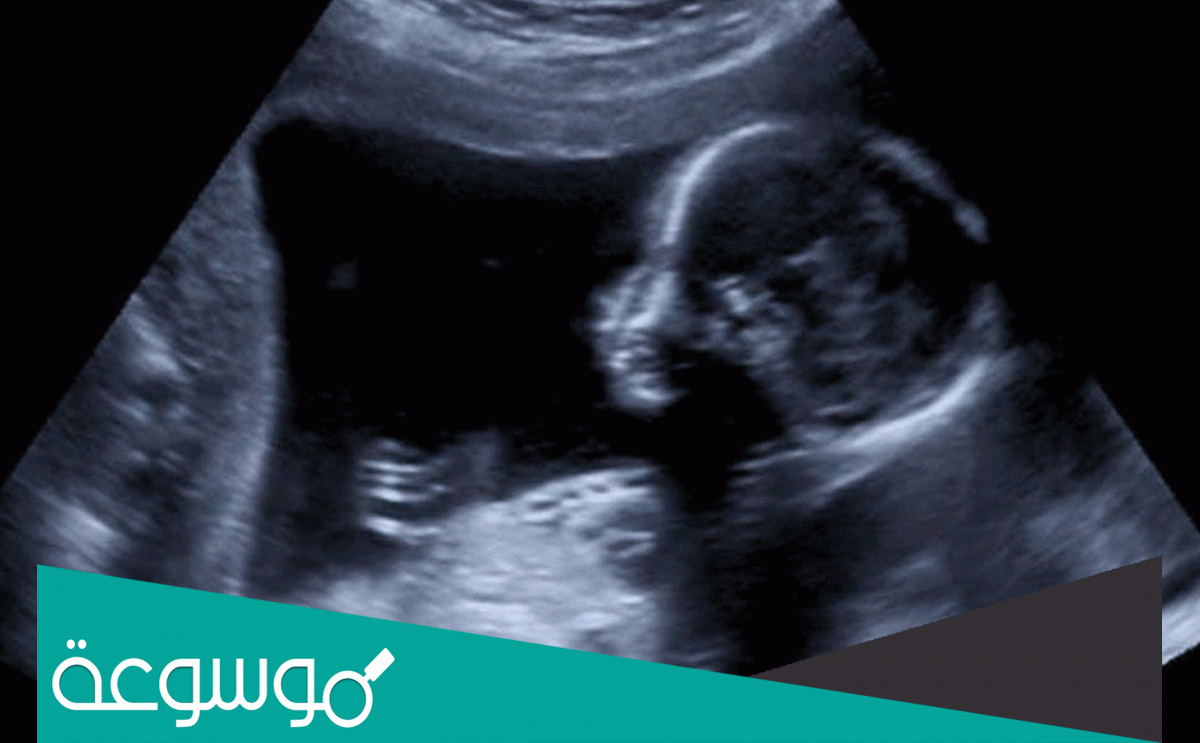

نبض قلب الجنين هو الدليل القوي على سلامة الجنين وأن نموه يسير بشكل طبيعي ويمكن للطبيب المختص قياس نبضات قلب الجنين من خلال الموجات فوق الصوتية

عندما يبدأ الأسبوع السادس من الحمل ، يبدأ تكوين الرئتين والفك والأنف ، وتحتوي براعم الأطراف (اليدين والقدمين) على بنى شبكية تشكل الأصابع ، ويمكن سماع دقات قلب الجنين من خلال الموجات فوق الصوتية المهبلية ، و – يبلغ طول الجنين في نهاية الأسبوع السادس حوالي نصف بوصة.

الأسبوع السادس من الحمل هو الأهم بالنسبة للأم ، حيث يمكن سماع أول نبضة قلب للجنين من خلال الموجات فوق الصوتية عبر المهبل ، والتي تبلغ حوالي 00 نبضة في الدقيقة ، ولا يستطيع الطبيب سماعها من خلال الموجات فوق الصوتية من خلال الدوبلر.

تظهر نبضات قلب الجنين من خلال الموجات فوق الصوتية دوبلر أثناء الحمل والتي تتراوح من الأسبوع الثامن إلى الأسبوع الثاني عشر.